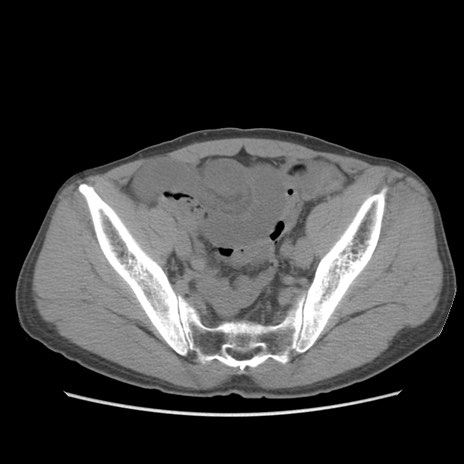

症例56 CT(横断像)

脂肪ウインドウ